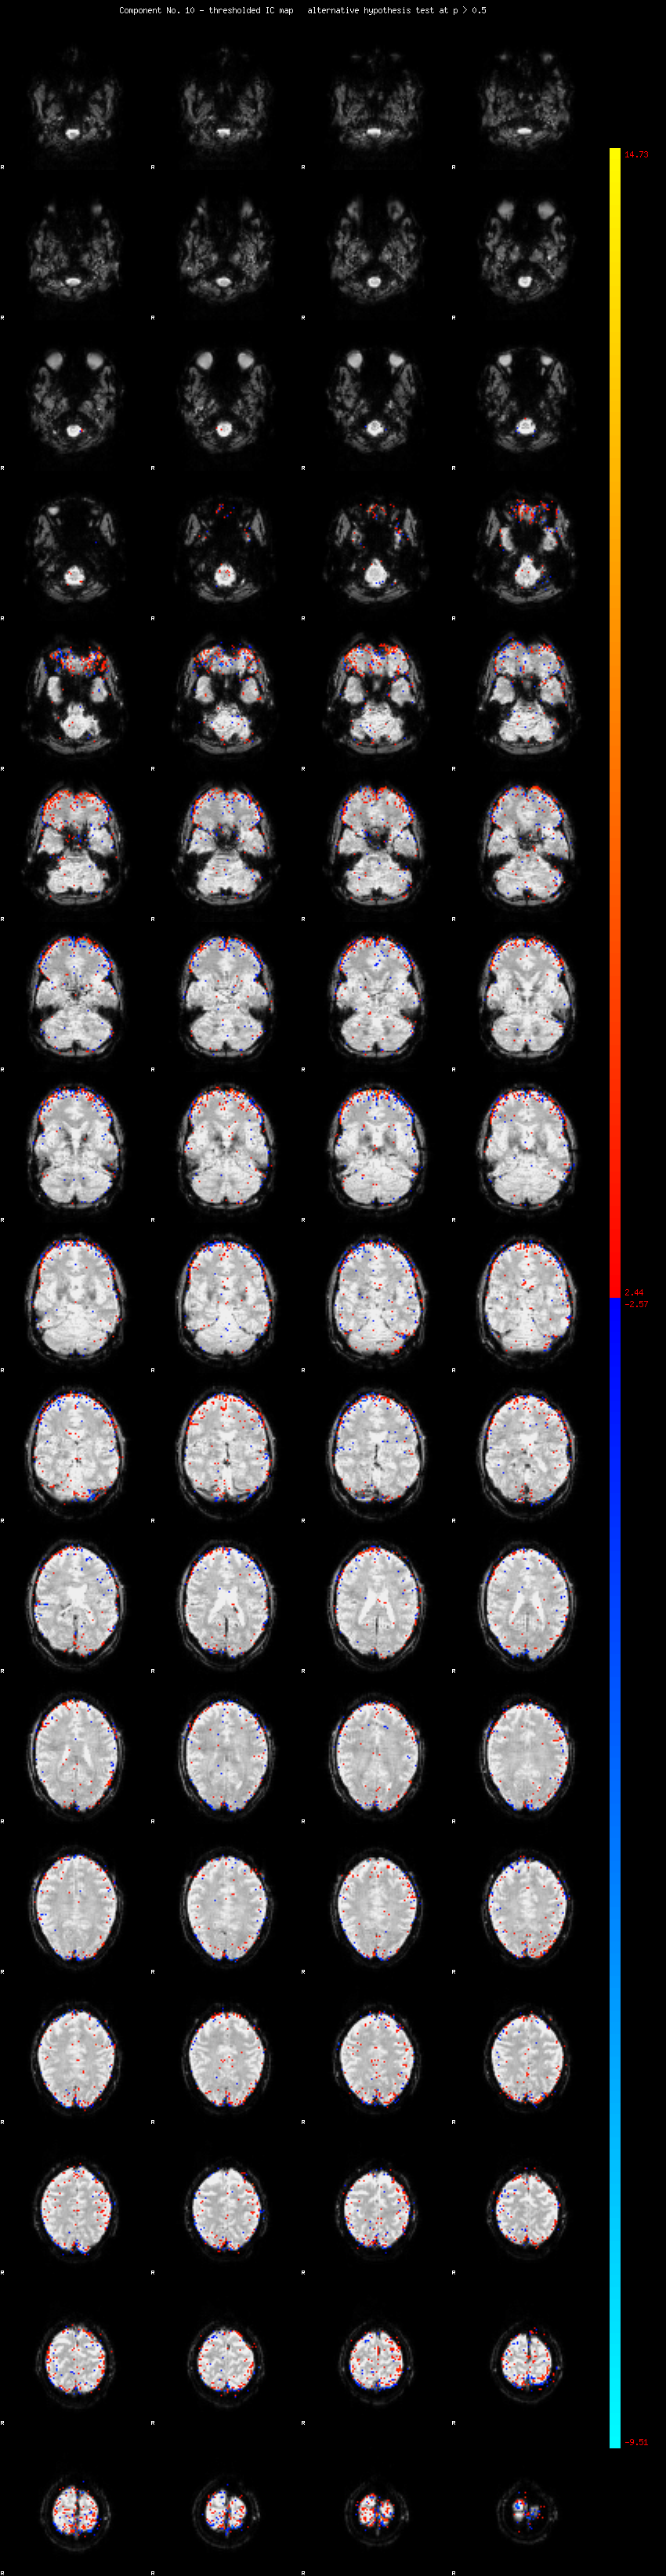

MELODIC Component 10

2.13 % of explained variance;     1.41 % of total variance